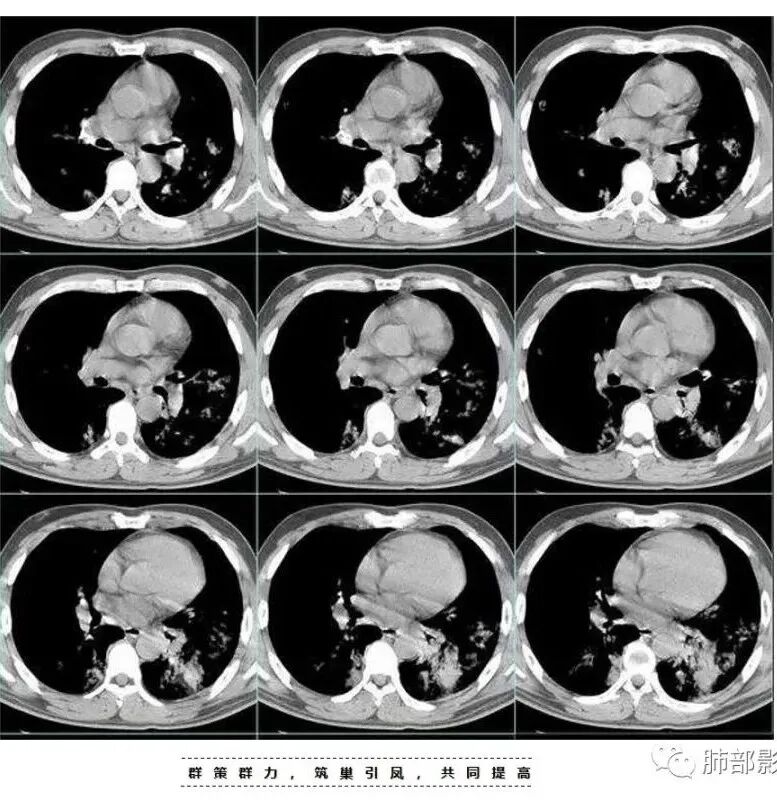

左下肺的囊腔呈簇状分布

这个区域应该是外侧最重的,但是没有看到空洞。二元论也可以,单纯从影像看金葡也不一定都是小叶性改变的,肺泡性改变也可以,从病史看,可能病毒合并金葡。

就是说这个基础病变不知道是什么,肯定有基础病变,不然不符合,因为前上个星期才去讲这个金葡的,当时一看,这个斑片斑片确实有金葡的一些特点存在,支气管壁有增厚。

这是气道早期金葡菌的特点

金黄色葡萄球菌为厌氧的革兰氏阳性球菌,可产生凝固酶和多种其他毒素及酶,其感染的病理改变中最突出的特点是化脓倾向强,尤其是MRSA肺炎具有起病急,病情进展快,病死率高的特点,早期诊断并进行足量、敏感的抗菌药物治疗对减少其发病率及死亡率具有重要作用。金葡菌肺炎常表现为多种CT征象并存,磨玻璃密度影及斑片影是最常见、最主要的CT表现,肺气囊是典型的影像表现。肺气囊是支气管周围脓肿使终末细支气管和肺泡发生坏死,当与支气管相通后坏死物质排空形成的含气空腔,表现为圆形或类圆形的薄壁空腔,壁厚1—2 mm。部分患者因起病急,使用抗生素较早,在一定程度上也影响了金葡菌感染的程度及转归,表现为磨玻璃样影及斑片影,因此在脓肿基础上形成的肺气囊亦相对较少或出现较晚。